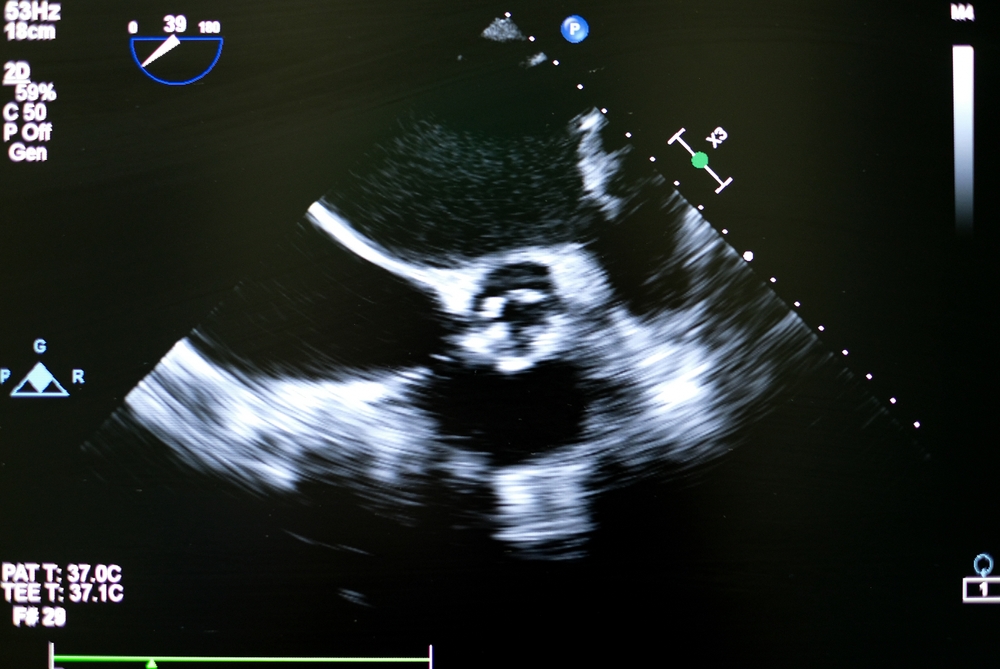

- Nowoczesny aparat USG – wysokiej klasy sprzęt pozwala na precyzyjną ocenę struktur serca i przepływów krwi.

- Badanie echo serca - leżysz na lewym boku, lekarz przykłada głowicę USG do klatki piersiowej. Badanie trwa zwykle ok. 15–30 minut.